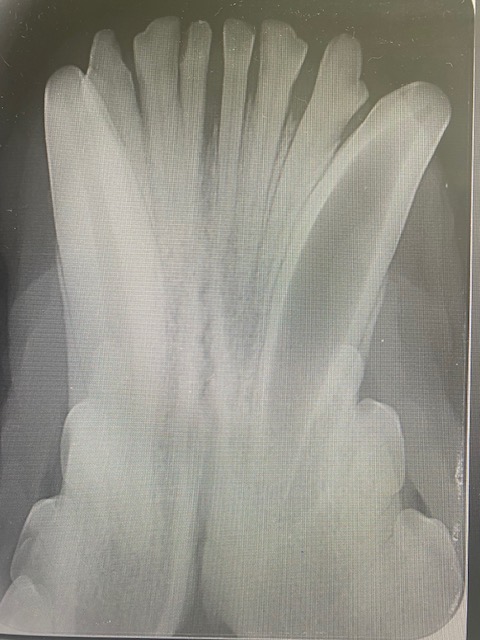

When under the anaesthetic the mouth could be properly examined, and a draining fistula identified at the point of the apex of the canine tooth, directly below 306. Pre op x-rays showed the the apex of the root of 304 was not closed. This means that most likely a traumatic incident occurred at the age of 9-12 months, causing the tooth to die and the normal development of the tooth to stop. As you can see in the x-ray, 304 has a much larger pulp than 404, indicating 304 is dead.